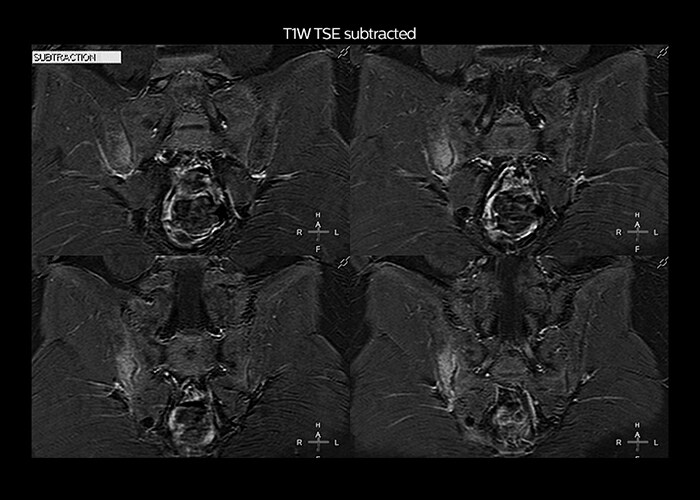

“On average, we scan about 80 patients per day, but on some days we scan well over 100 patients. The scanner is in use 7 days per week, operated 20 hours per day on week days and 8 hours per day in the weekend,” Mr. Tuna says. “To avoid coil changes we plan examinations of similar anatomies back to back, such as head and spine. Multiva helps us here a lot because coils don’t need to be changed frequently. Moreover, thanks to parallel imaging technology and 16-channel HeadSpineTorso and 8-channel MSK coils we are able to achieve excellent image quality. In this way Multiva helped us to increase both image quality and productivity.” “Neurological cases, such as brain and spine imaging, represent the largest share in our MR scanning, followed by musculoskeletal cases. In general, we use simple and basic imaging protocols. But occasionally, we use advanced techniques for problematic cases if necessary.